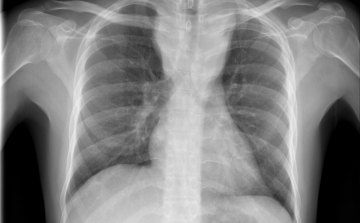

Szinte minden tüdőrák a dohányzásból ered

Több mint húsz betegség gyűjtőneve a tüdőrák, az egyik leggyakoribb és legveszélyesebb rosszindulatú betegség Magyarországon.

A tüdőrák legkorábbi jelei

A tüdőrák a tüneteinek jelentkezése előtt is nagy százalékban felismerhető, amennyiben rendszeresen részt veszünk a megfelelő szűrővizsgálatokon.